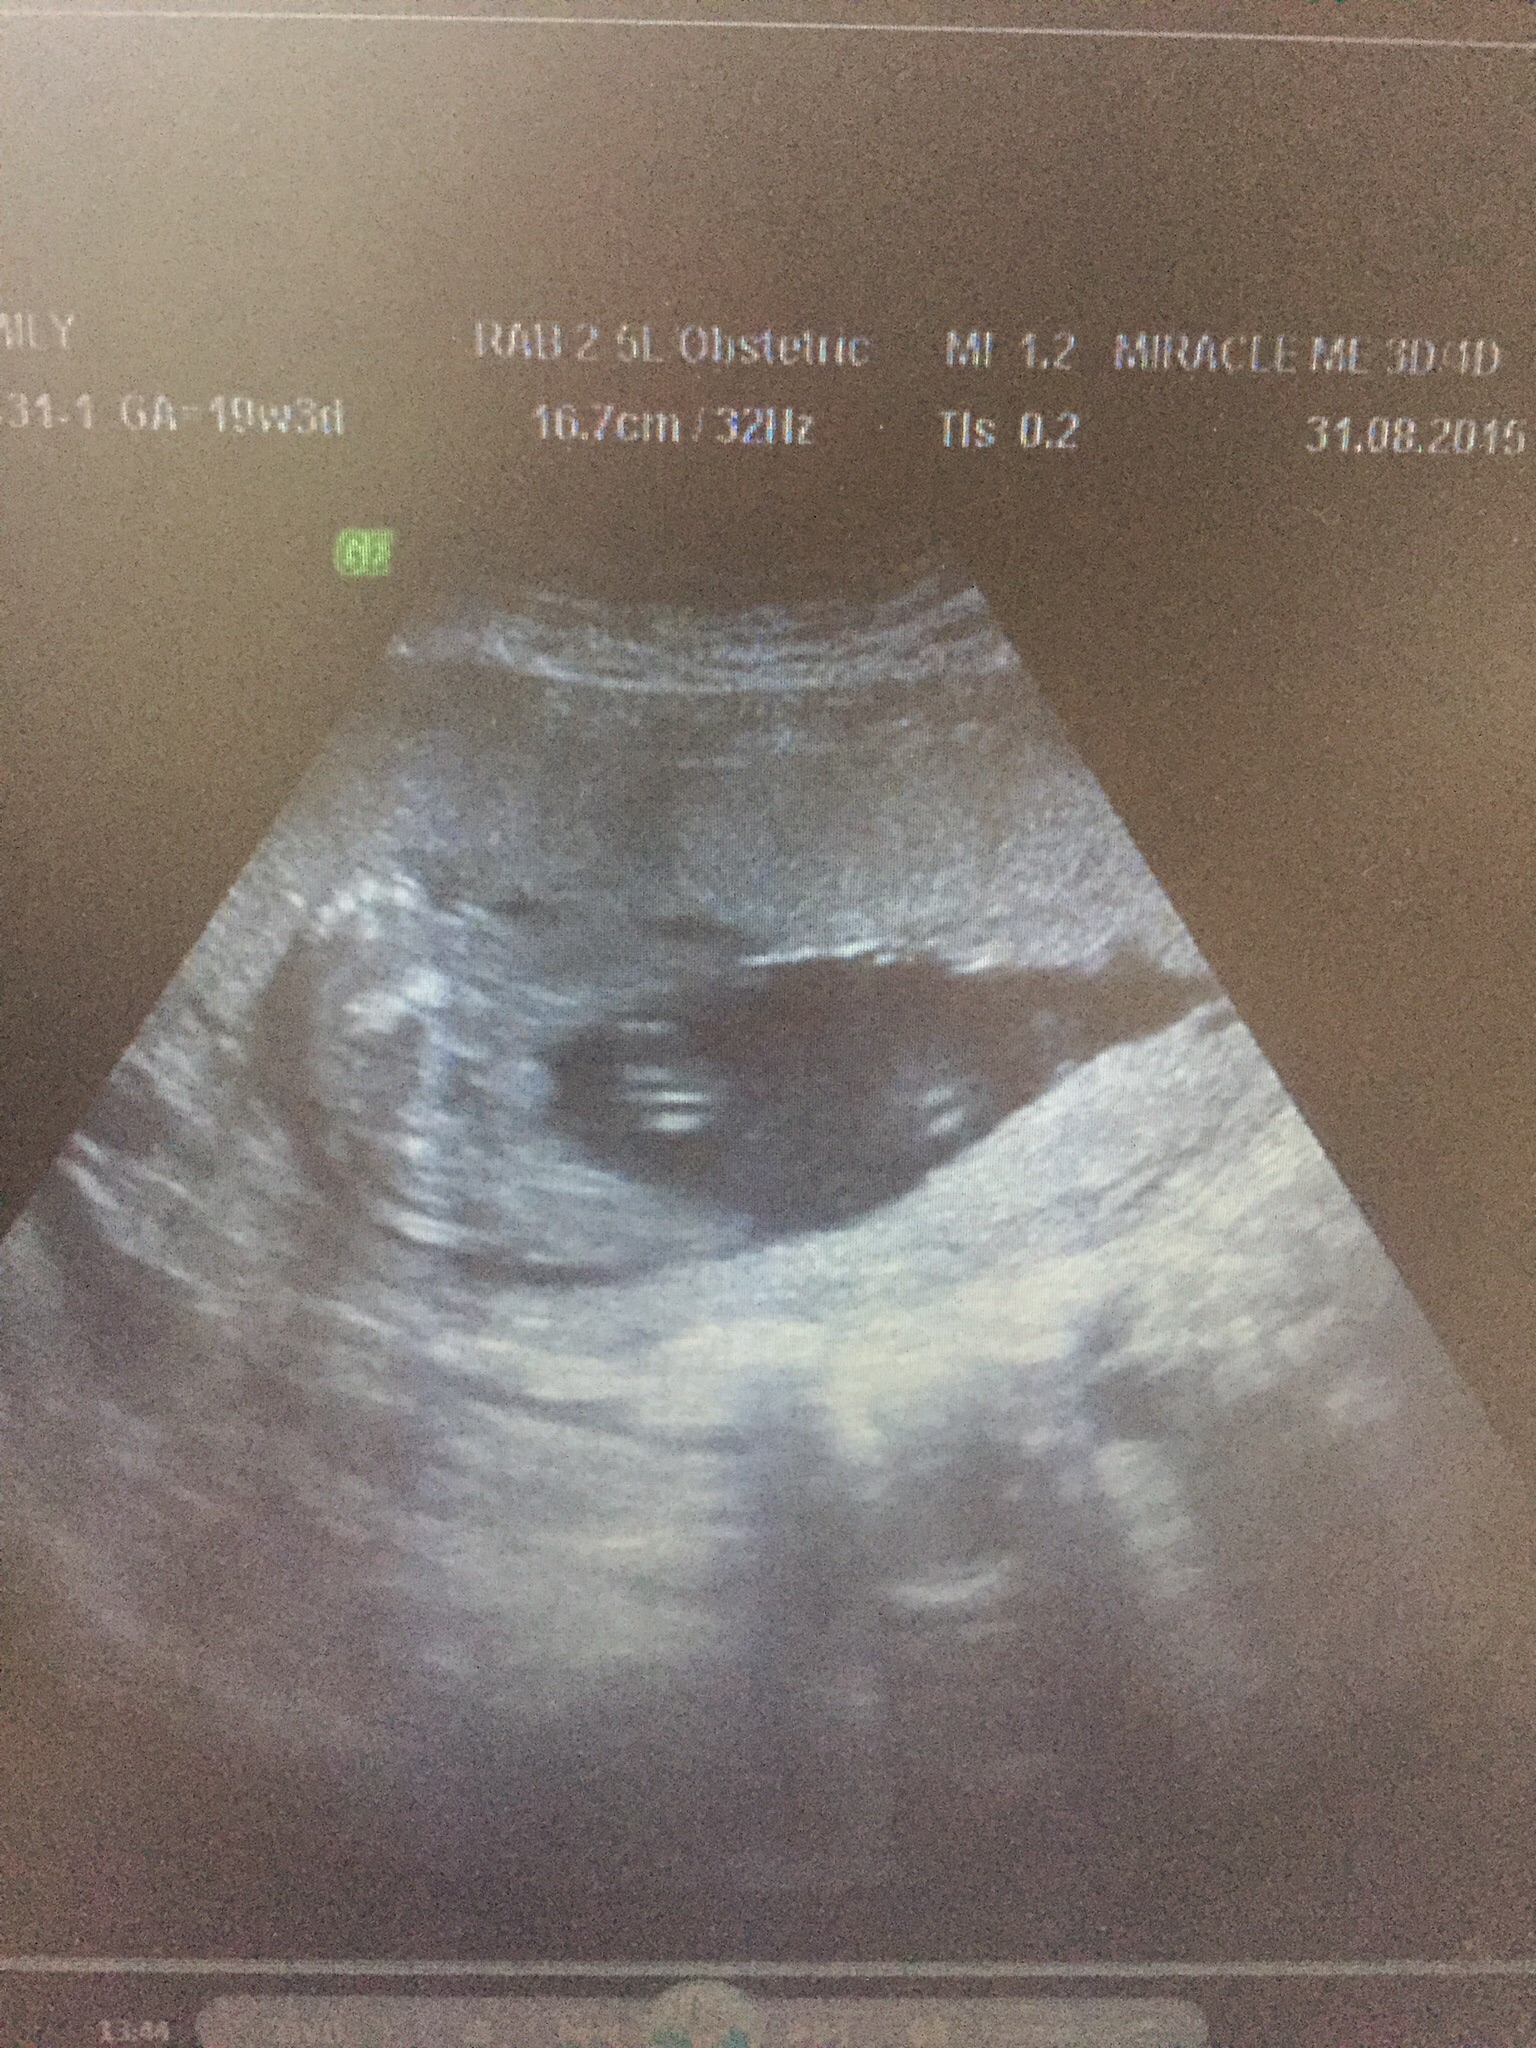

Attachment 27333These are 2d & 3/4 d scan pictures at 19 weeks 3 days any guesses?? Please? Attachment 27332

The bottom one is a classic hamburger pic! Girl! [emoji178]